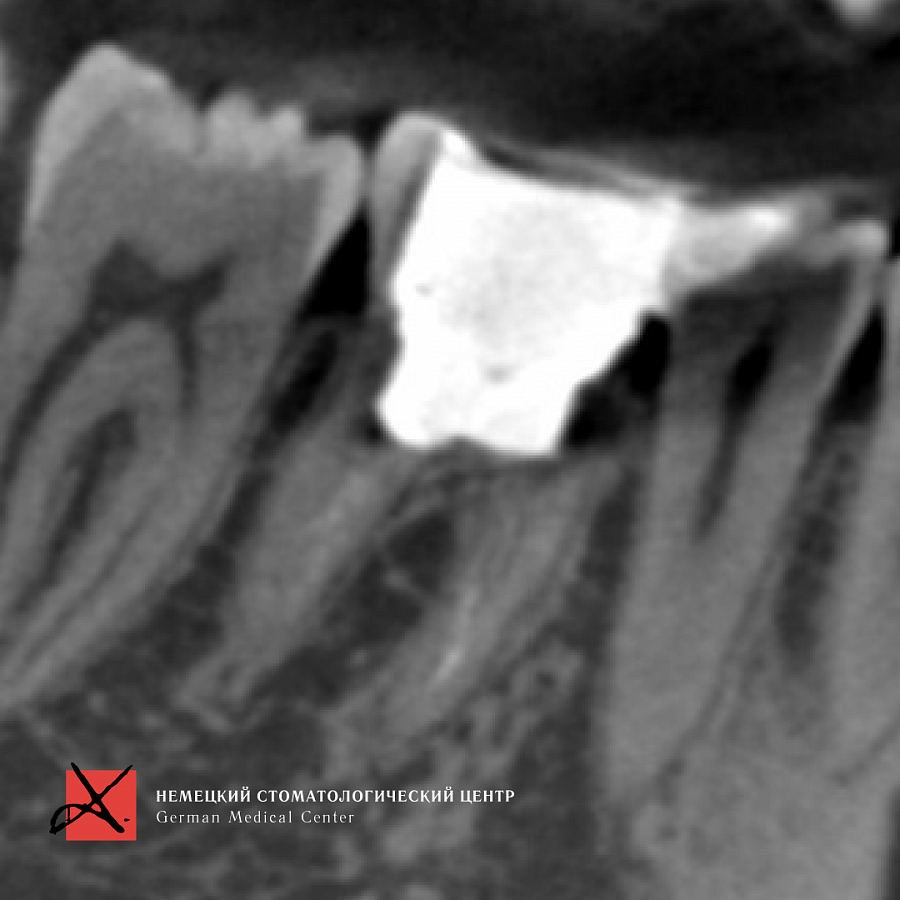

Пациент направлен врачом-терапевтом для удаления зуба 46 (нижний шестой зуб справа) и одновременной постановки имплантата.

Зуб был фрагментирован, чтобы удаление прошло максимально атравматично, то есть без повреждения окружающих костных стенок. После удаления установлен имплантат. Операция прошла успешно, пациенту уже установлена зубная коронка.